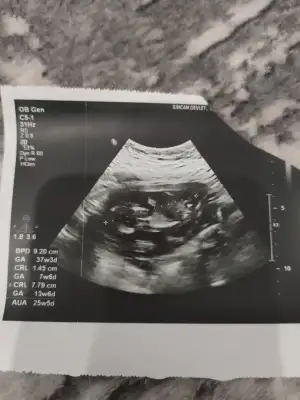

Seninle sat başlangıcımız aynı haftaya hangi gün gitceksin cnm herkes bana 13+3 de öğrenmek için çok erken diyoda ondan soruyorum.Kızlar tekrar merhaba şimdi doktordan çıktım 2 3 gün geriden gelen bebişim 2 gün öne geçmiş, ikili tarama için kan verdim burun kemiği oluşmuş ense kalınlığı 1,4 dedi gayet güzel dedi veeee haftaya kesin net diyebilirim ama şu an erkek görünüyor dedi ben de oğlan anası olacağım galiba